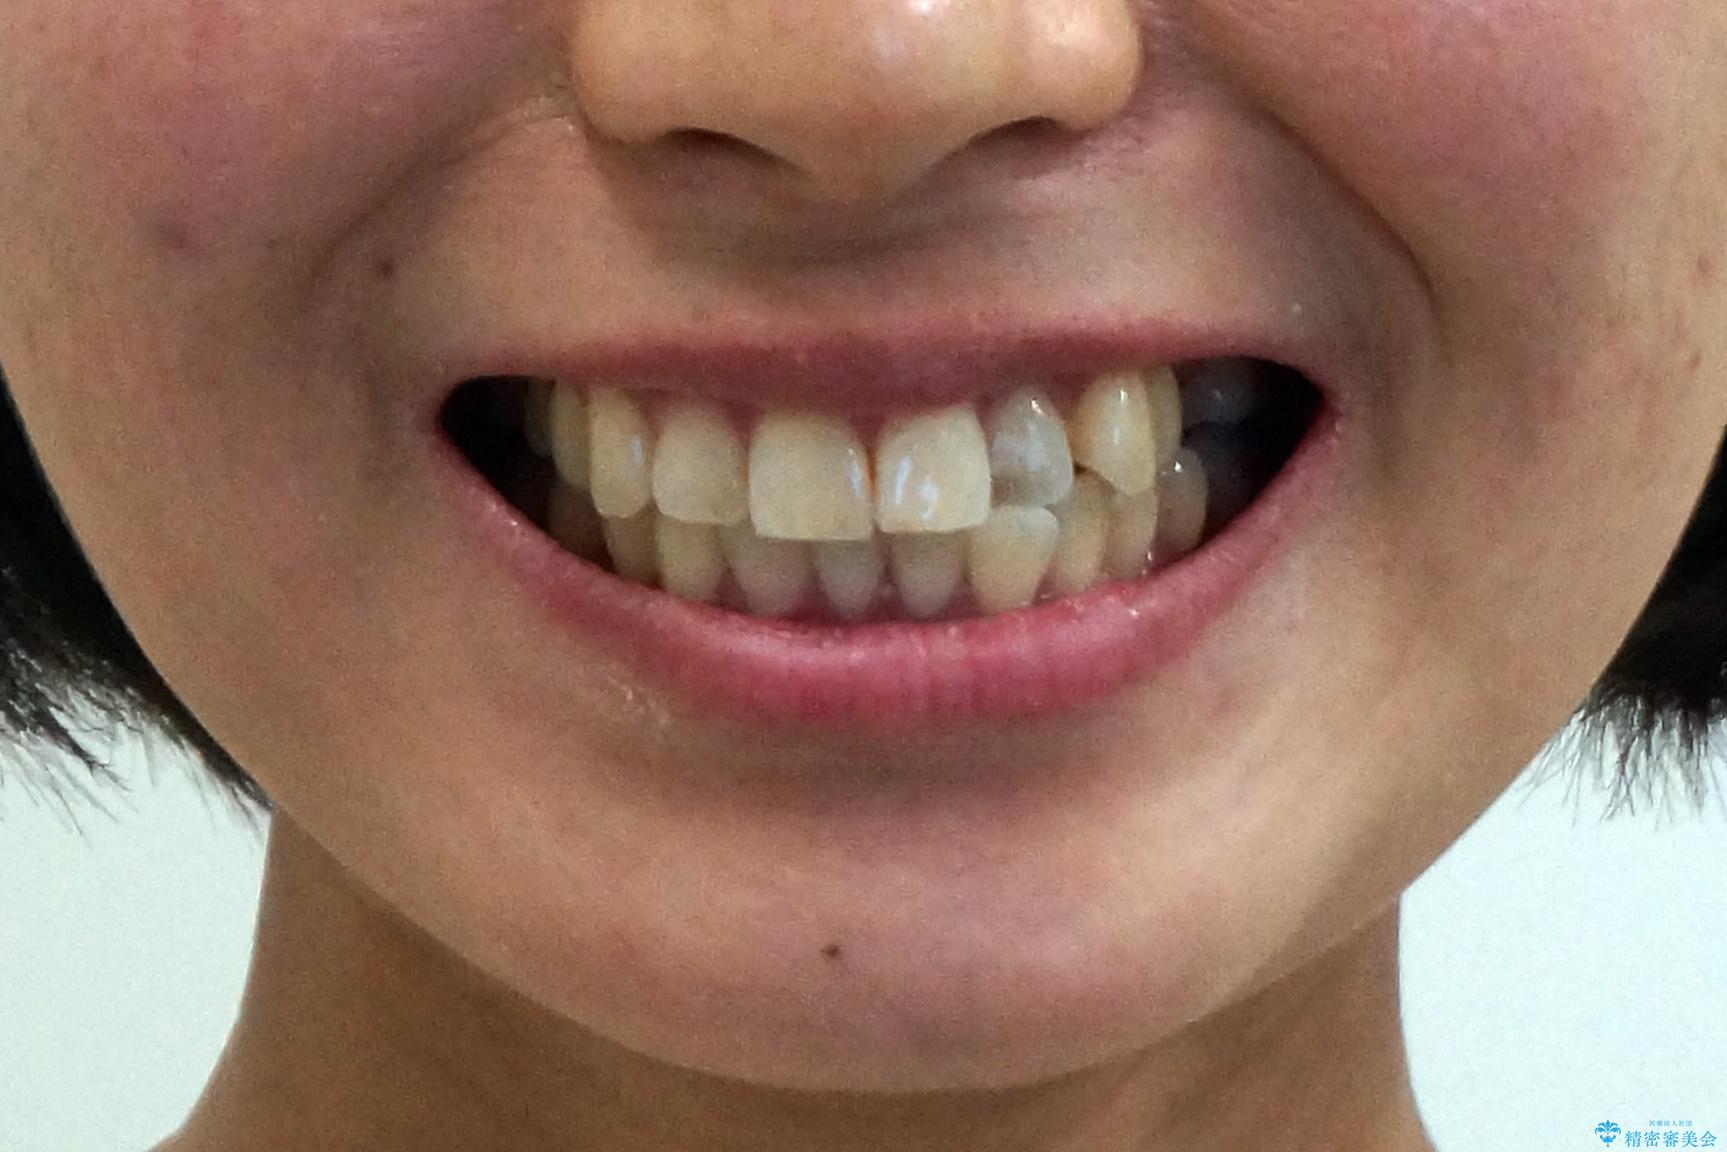

前歯と奥歯の反対咬合 部分ワイヤーとインビザラインで

- 前歯の並びを気にして来院。

左上の前歯が内側に入って反対咬合になっていました。

また、左上5番も反対咬合でした。

上のワイヤー矯正を半年ほど行い反対咬合を改善してから、上下インビザライン治療を行いました。

下の前歯を中に入れるためにIPR(歯をわずかに削る処置)を行いました。

左上の反対咬合になっていた歯の頬側咬頭は、すでに削れて短くなっていましたがそのまま並べています。